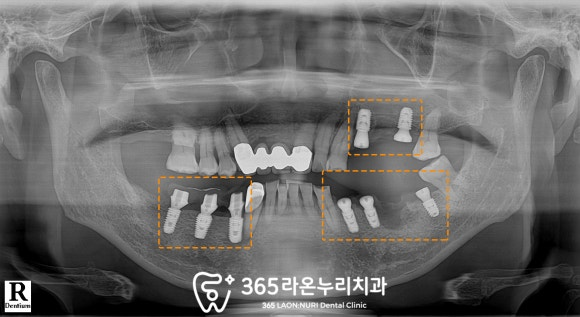

■ 2. 엑스레이 검진

파노라마에서 보이는 것과 같이

자연치가 결손된 부위가 있어

오른쪽으로는 식사를 잘 하지

못하시는 상황이었으며

이외에도

치주 질환으로 잇몸뼈가 녹고

뿌리 끝에 염증이 생겨있는 이도 있었습니다.